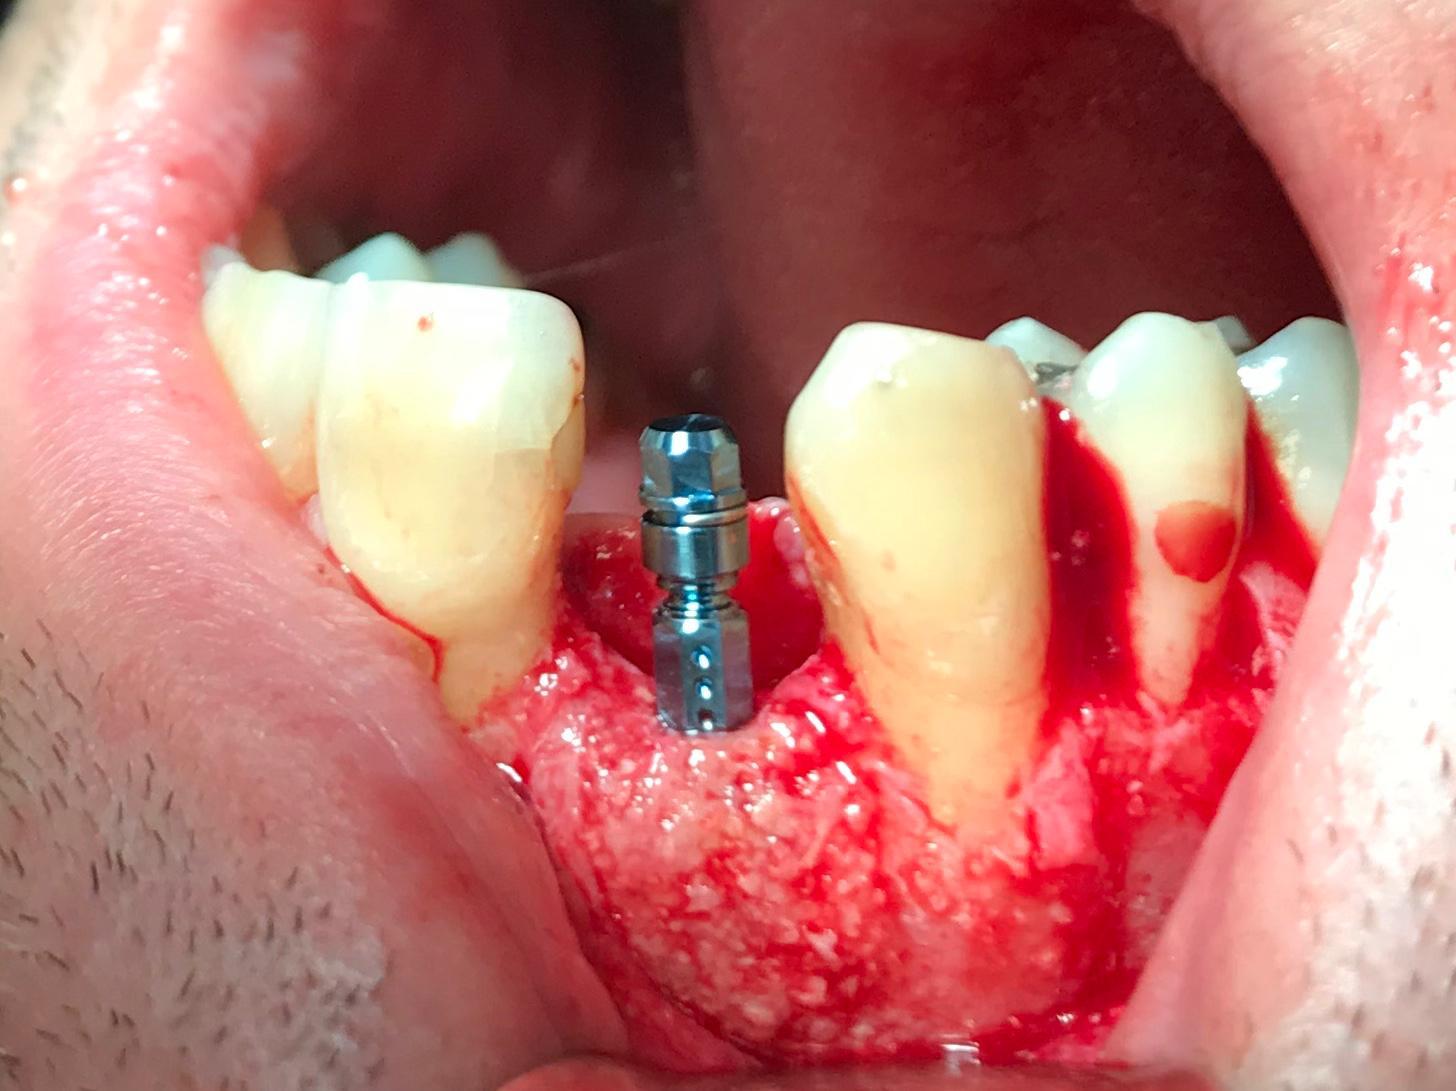

Immediate implant placement with simultaneous bone augmentation and connective tissue grafting. The case will be completed with crown lengthening, veneer replacement, and soft tissue optimisation to achieve ideal emergence profiles.